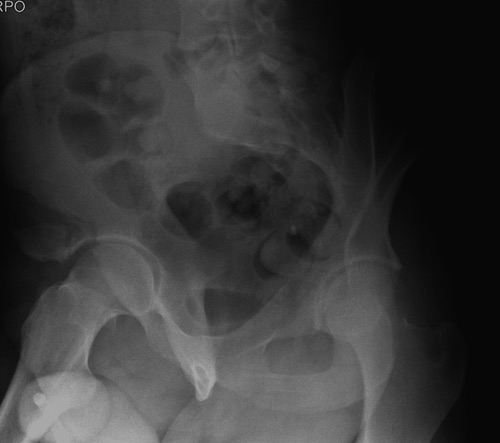

Дискуссия показывает интересные стороны развития тактики лечения переломов вертлужной впадины. Для разработки лечебной тактики сперва надо установить диагноз, и разбор показывает, что не все справляются с такой задачей! Изучение перелома надо начать из стандартных снимков: для переломов костей таза: прямой, inlet и outlet, а для перелома вертлужной впадины - снимки по Judet.

В последнее время, из-за красоты участился показ 3D снимков, хотя надо начать c обычных, и, по необходимости, компьютерная томография с 3D! Без головки бедра 3D покажет общую картину и вовлечение сустава, а более детально только в срезах КТ.

Данная картина показывает очень редкий перелом передней колонны, но перед операцией еще раз надо просмотреть обещанные дополнительные КТ срезы.

Представленные слайды Александром из Севастополя, имеет ценность, но, кроме inlet, остальные стандартные Judet рентген снимки должны показать правоту принятого решения. Возможно, здесь фиксация перелома вертлужной впадины, но по рентгену трудно понять!

Фиксация переломов передней колонны намного легче, чем остальных переломов вертлужной впадины. Любой доступ: Smith Petersen, Stoppa или ilio-inguinal. Как фиксировать перелом зависит от желания врача, можно пустить пластину по pelvic brim (linea terminalis) или более щадящее из верхнего окна пластиной, а переднюю колонну длинными межколонными винтами.

Здесь пример перелома передней стенки, где сохранен принцип фиксации передней колонны. Для доступа Smith Petersen с остеотомией ASIS. Мышца сарториус отодвинута, и сделана ре-фиксация на свое место винтами. При хорошем обзоре, наличие Farabeuf или Jungblud forceps облегчит репозицию.